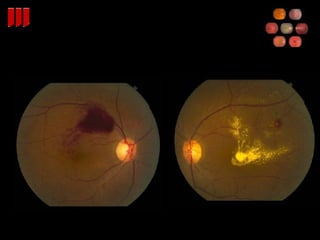

35 yo on multiple BP meds

Hypertensive Retinopathy Describe fundus findings associated with hypertensive retinopathy? Constriction of retinal arterioles Intraretinal hemorrhages Cotton wool spots Macular edema Disc edema Retinal neovascularization What are manifestations of hypertensive choroidopathy? Elschnig spots and Siegrist streaks

35 yo onmultiple BP meds

Hypertensive Retinopathy Describefundus findings associated with hypertensive retinopathy? Constriction of retinal arterioles Intraretinal hemorrhages Cotton wool spots Macular edema Disc edema Retinal neovascularization What are manifestations of hypertensive choroidopathy? Elschnig spots and Siegrist streaks